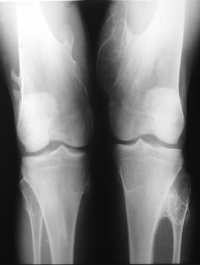

X线表现为骨性病损自干骺端突出,一般比临床所见的要小,因软骨帽和滑囊不显影,肿瘤的骨质影像与其所在部位干骺端的骨质结构完全相同。不易区别。位于长骨的肿瘤其生长方向与邻近肌肉牵引的方向一致,例如股骨远端的骨软骨瘤向股骨的生长,胫骨近端的肿瘤向胫骨远端生长。其形状不一,可有一个很长的蒂和狭窄的基底。或很短粗呈广阔的基底,较大的肿瘤其顶端膨大如菜花,悬垂状骨性骨块,其尖端朝向邻近关节相反方向。其基底直接或有一细蒂与骨皮质相连续。瘤体表面的软骨帽虽然在X线上不显影,但常有钙化和骨化位于前臂小腿的较大肿瘤可压迫邻近骨骼,产生压迫性骨缺损或畸形。多发性者往往合并骨骼畸形。

1.X线表现:表现为附着于干骺端的向外骨性突起,生长方向与肌肉的牵引方向一致,与受累骨皮质和松质骨相连,软骨帽不显影,有长蒂型和广基型之分。

多发性骨软骨瘤表现为干骺端增粗,皮质变薄,肿瘤外形不一,常出现患骨关节畸形,当肿瘤恶变时,其表面的软骨部分迅速长大,当有大量钙化时,则X线表现明显。